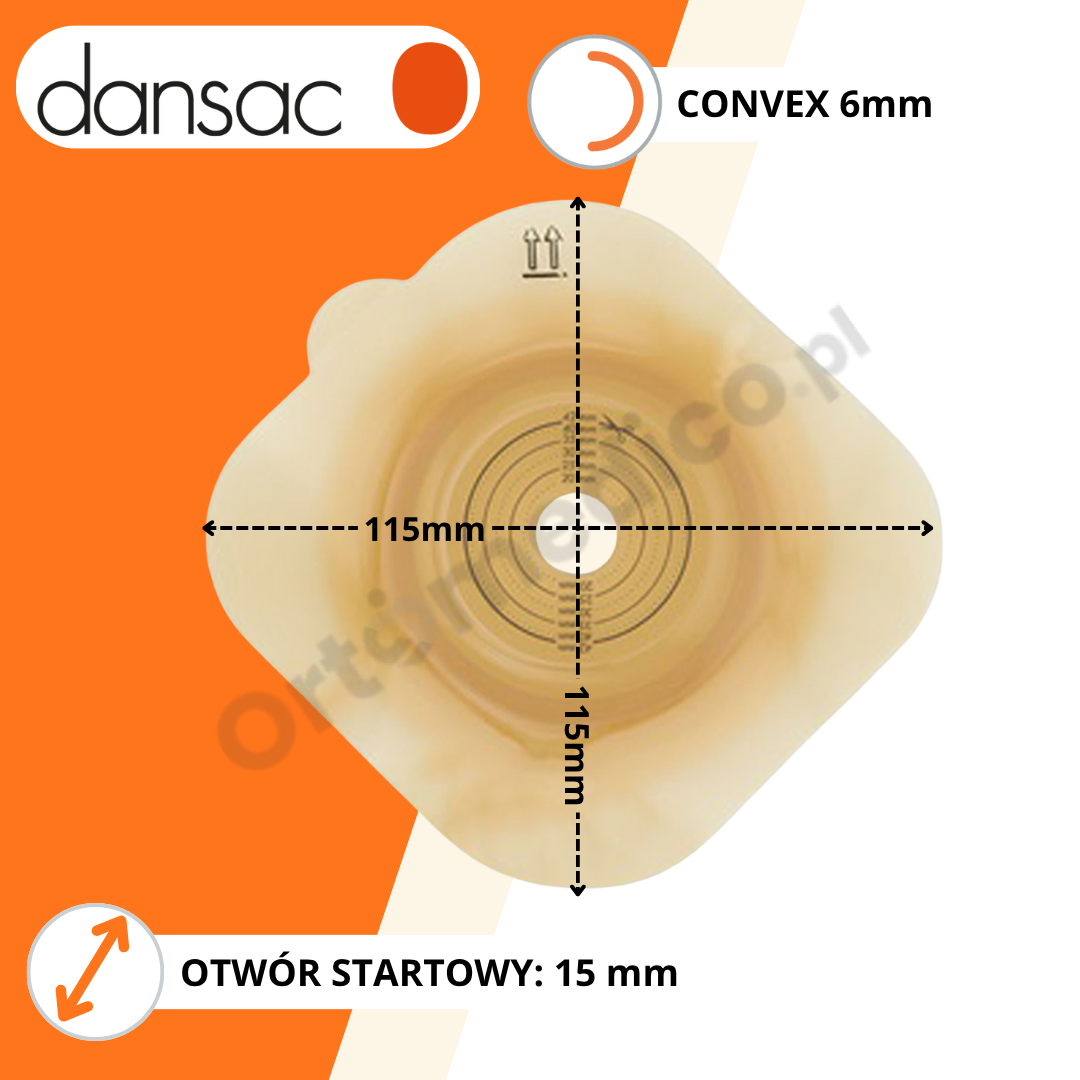

Wymiary Płytki 1555-15 Dansac Nova 2 Convex:

WYPUKŁOŚĆ: 6 mm

OTWÓR STARTOWY: 15 mm

DO PRZYCIĘCIA: 15-42 mm

WYMIAR PŁYTKI (wys. x szer.): 115x115 mm